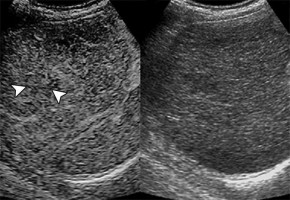

Lead investigator Manxia Lin of China's Sun Yat-Sen University retrospectively studied 39 consecutive patients with 44 pathologically confirmed cirrhotic nodules who initially underwent contrast-enhanced ultrasound (CEUS) examination at detection, followed by conventional ultrasound every 3-4 months thereafter.

Fourteen nodules (31.8%) evidenced eventual malignant transformation after a median follow-up time of 26.7 months.

According to Lin and colleagues' results, the contrast arrival time difference between the cirrhotic nodule and the liver on CEUS proved useful in stratifying eventual malignant transformation risk--"which may enable a more customised surveillance strategy," they noted.

"During surveillance," Lin et al. continued, "a relative growth rate of 30% or greater in 6 months or an absolute growth rate of 5 mm or greater in 6 months highly indicated malignant transformation."

Image Source: AJR